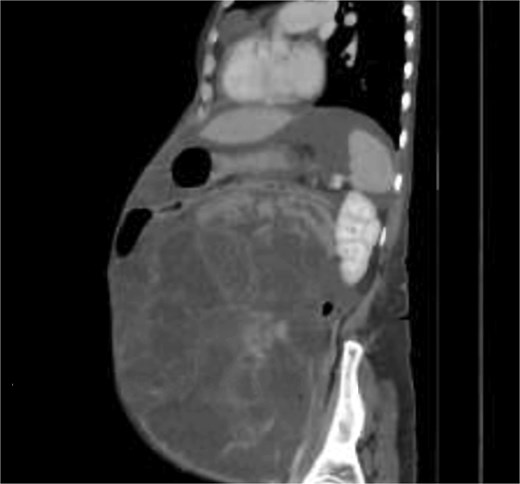

A 58-years-old female previously healthy, presented with gradual increase in the abdominal circumference and a massive weight loss of 17 kg over the past 6 months (Body Mass Index, BMI = 18). She had her menarche at 13 and her menopause at 41. The patient conceived one child without fertility or hormone therapy. Computed tomography (CT) showed an enormous abdominal tumor with minor peritoneal effusion, atelectasis, and pleurisy over the right lung (Figs 1 and 2).

The patient was scheduled for a diagnostic laparoscopy which revealed 3 L of ascites, no peritoneal carcinomatosis and a large polylobate partially cystic tumor arising from the pelvis. The mass was resected in one piece through xypho-pubic laparotomy. It weighted 9 kg (240 × 180 × 235 mm) and had relatively thick walls attached to the left ovary (Figs 3–5). A concomitant total hysterectomy, right adnexectomy, omentectomy, and appendectomy were performed with multiple biopsies from the Douglas, liver, omentum, mesenteric, peritoneal, and pelvic walls.